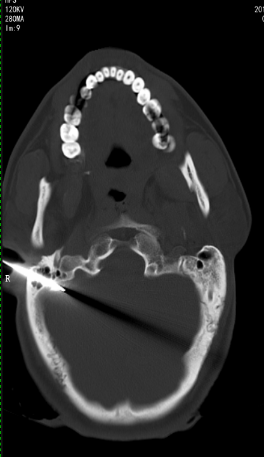

3月10日早晨8点左右,一对夫妻因头部多处刺伤被送120送入西安凤城医院急诊科接受治疗。丈夫被一把尖刀从右耳直接刺入,并且刀具断入颅内(图1、图2),妻子为开放性颅脑损伤、颅骨粉碎性凹陷骨折,当即昏迷,夫妻二人生命垂危。入院时丈夫不省人事,脉搏心跳十分微弱,急诊科医师立即对夫妻二人进行了相关检查,同时积极联系神经外科将病人转入神经外科继续抢救。神经外科王冰主任查看病人及检查结果之后,表示夫妇二人均为“重型颅脑损伤”,病情危重,随时有生命危险,必须立刻手术。家属听王冰主任讲述病情、手术方式、风险及可能出现的并发症后,积极要求手术。

图1 (残留的刀具)

图2 (CT显示刺入颅内的刀具)